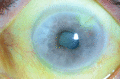

We report a very unusual presentation of primary intraocular lymphoma masquerading as anterior uveitis with atypical symptoms. A 68-year-old man, initially presented with a 4-day history of painless, left blurred vision. Examination revealed 2 or more anterior chamber cells, mutton-fat keratic precipitates and posterior synechiae. Treatment was initiated, the eye settled, and the patient was discharged. He re-presented 7 months later with hypopyon, a hazy cornea, fibrin deposits and a narrowed anterior chamber angle. Over the coming weeks, it became apparent that the temporal iris was thickened, involving the angle, and his intraocular pressure increased despite topical dorzolamide. Following advice from a tertiary centre and referral to a regional ocular oncology centre, a transscleral biopsy was performed and suggested a ciliary body melanoma. Enucleation was advised and performed, with histological examination revealing features consistent with an ocular diffuse large B-cell lymphoma not involving the optic nerve, sclera or cornea. This is the first ever published report of a case of ocular lymphoma masquerading in this way.